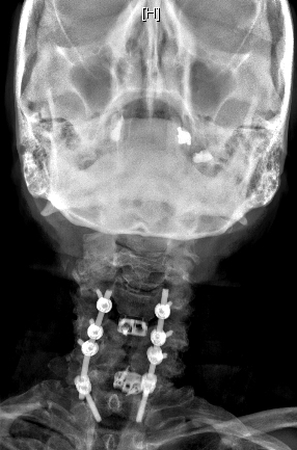

July 29th 8 Stainless Bolts, 2 Titanium Rods & 2 Implants